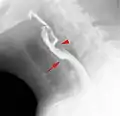

Web with "jet-phenomenon". Arrowhead on incomplete opening of the upper esophageal sphincter.

Esophageal web stenosis in barium swallow examination frontal view.